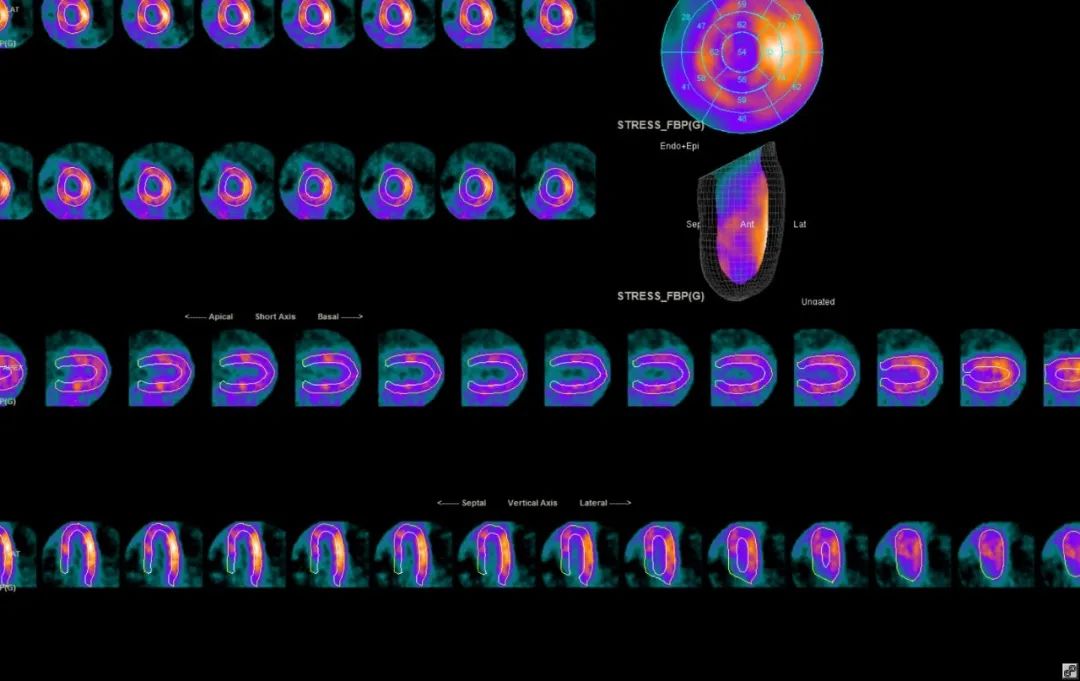

近日,我院核医学科与心内科合作为两例疑难冠心病患者进行瑞加诺生药物负荷心肌血流灌注显像,这为冠心病导致的心肌缺血、心肌梗死等提供了更为精准的诊断,为患者的后续治疗提供了有力保障。核医学科这一新技术应用于临床,使我院在心脏领域的诊疗水平继续提升,同时标志着我院在无创性冠脉功能学评估技术上迈上了靶点精确、安全有效的新台阶。

核素心肌灌注显像检查是国际公认的无创的直接反映冠状动脉供血心肌的血流灌注状态的方法,包括静息和负荷两种类型,静息显像的目的是观察安静状态下患者心肌血供的情况,而负荷显像则可以观察患者冠状动脉的储备功能障碍。

其中负荷显像又分为运动负荷和药物负荷。运动负荷的目的在于观察在心肌耗氧量增加时,病变的冠状动脉是否会引起局部供血不平衡。药物负荷是运动负荷试验的有效替代,且随着医学进步,患者风险与感受明显改善,越来越受到重视。